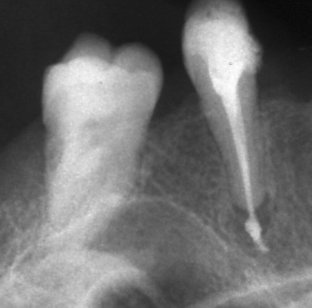

Запълване с препресване

Ендодонтия